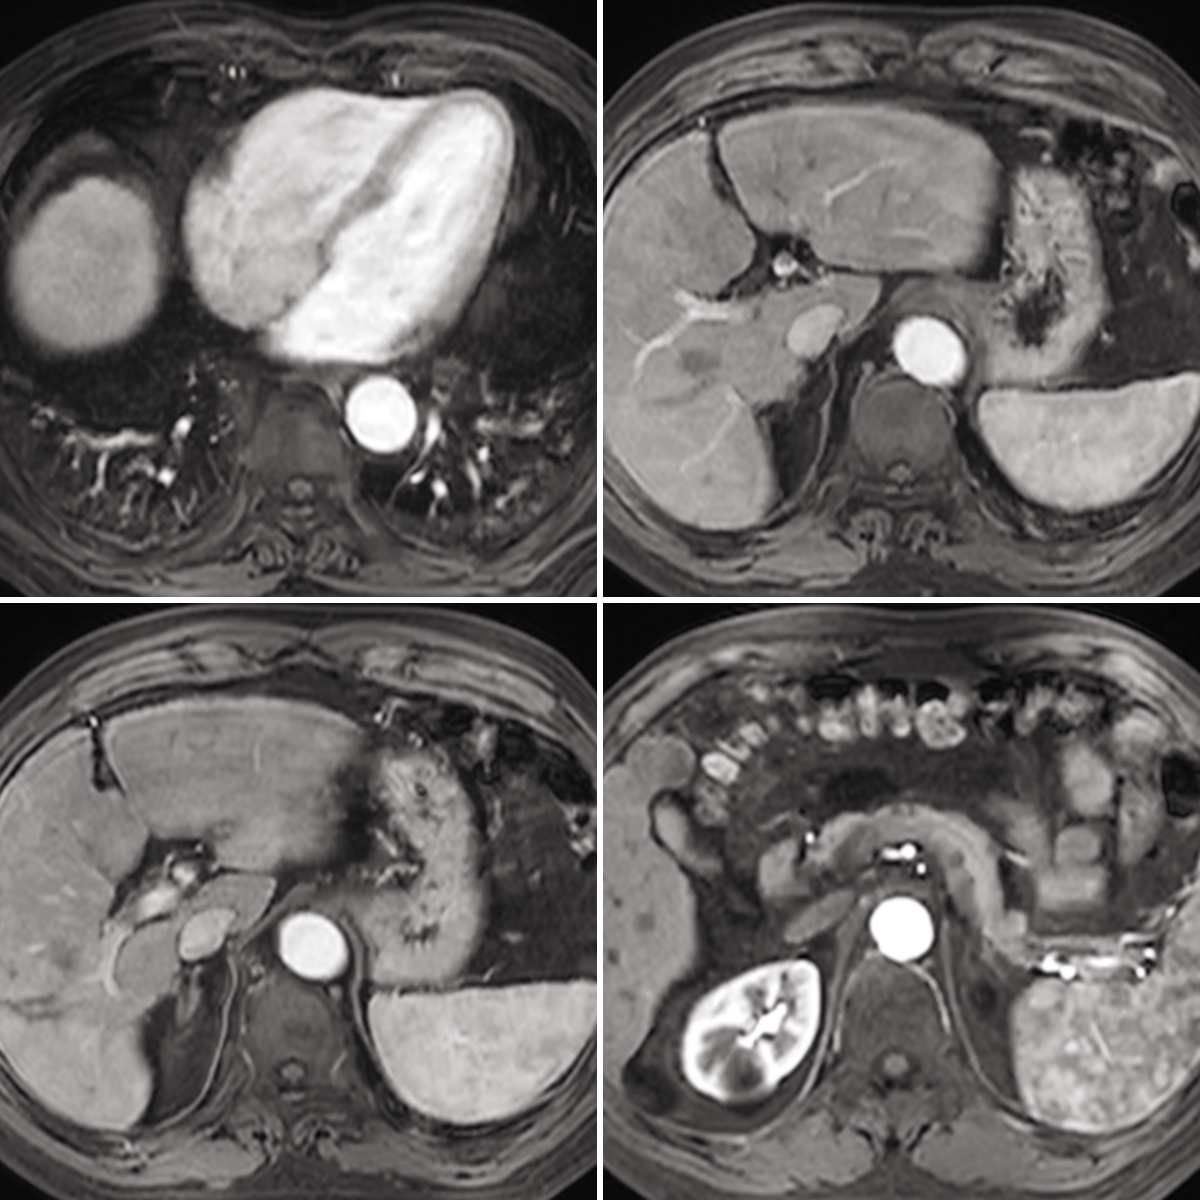

经过4个周期的治疗,2024年9月患者复查MRI提示肝内病灶强化均明显消失,仅胆囊床旁病灶体积较前增大。经过我们肝胆疾病诊治团队再次讨论,认为患者肝脏肿瘤得到有效控制,胆囊床旁病灶还有残存活性,可手术切除胆囊床旁病灶后继续综合抗肿瘤治疗预防复发。2024年9月13日在全麻下行腹腔镜下肝肿瘤切除术,术后病历提示肿瘤大部分坏死,部分可见活性肿瘤组织,切缘阴性。目前患者已恢复出院。

(治疗后)